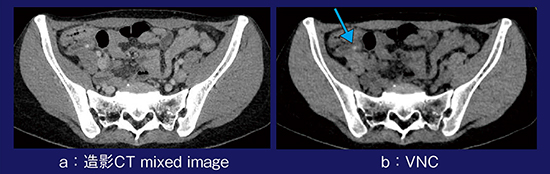

症例1は,39歳,女性,右下腹部痛の症例である。Dual Energyによる造影CT mixed image(120kVp相当)の画像では,さまざまな構造物が造影され病変がはっきりしないが,仮想単純画像を追加することで造影効果が除去され,虫垂結石が確認できた(図1)。

図1 症例1:仮想単純画像による虫垂結石の描出

症例2は,30歳,女性,同じく右下腹部痛の症例である。造影CTで認められる高吸収域は,造影された腫瘍であるかどうかがはっきりしないが,仮想単純画像でもやはり高吸収であり,腫瘍ではなく卵巣出血であると判断できた(図2)。

図2 症例2:仮想単純画像による卵巣出血の描出